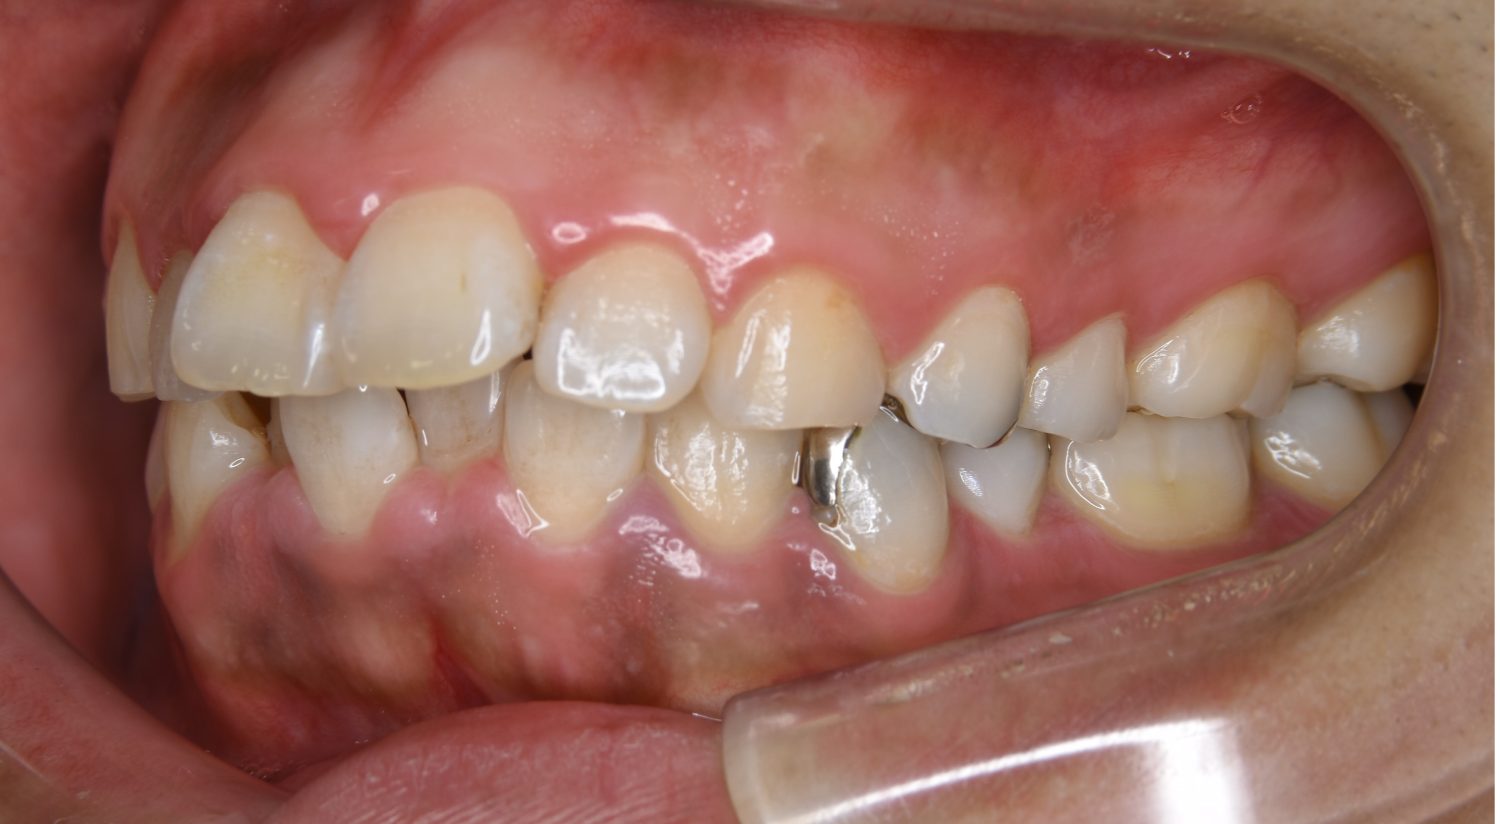

Before

主訴

前歯が開いているのが気になる。

治療内容

上リンガルブラケット(舌側装置)、下ラビアルブラケット(唇側装置)に矯正用アンカースクリューを併用し非抜歯で治療を行いました。

治療費

1,200,000 円(税込)

治療期間

33ヶ月

通院回数

34回

想定されたリスク

※歯根吸収、歯肉退縮、歯髄壊死、顎関節症状

上下の前歯が開いており前歯では全く噛めていない状態でした。臼歯の圧下を行うことで前歯でも咬合できるようになり機能面のみでなく審美面も著しく改善しました。